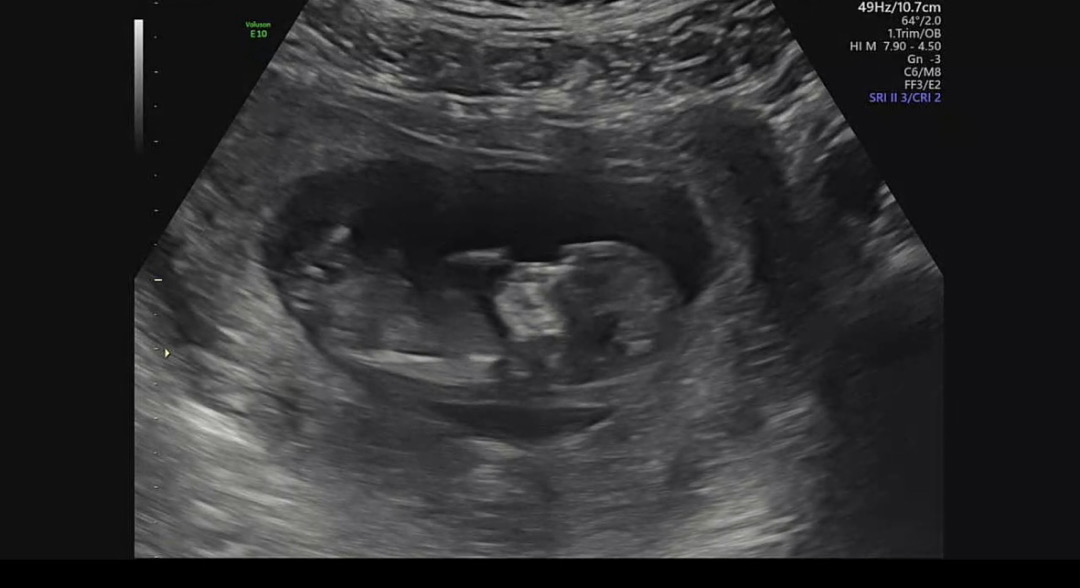

각도법!

화질이 안 좋긴 한데 그래도 추측해주세요!!